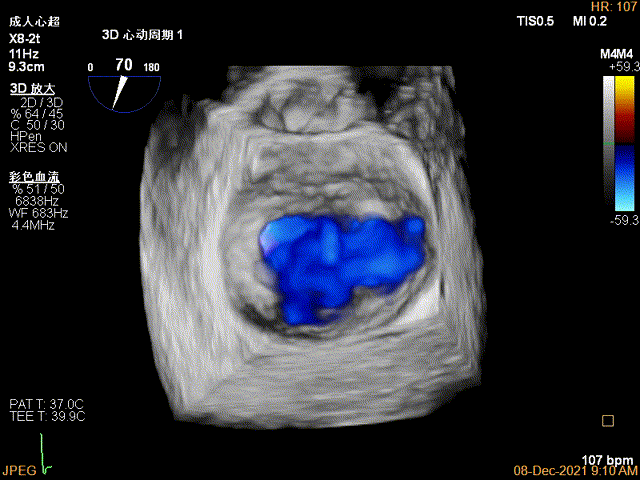

3D视图菲薄的卵圆窝,穿刺点位近似于3点位

3D-VIEW验证结果

3D-Color-view验证残余分流位于外侧